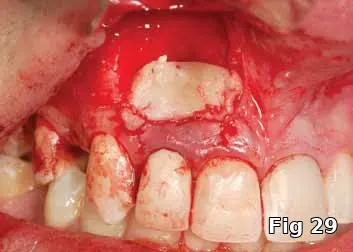

Here is a 24-year-old male with an ASA1 medical status who presented for the treatment of an apical lesion prior to prosthetic replacement of the failing existing restoration secondary to recurrent decay. Treatment plan to perform an apicoectomy and retrofill with MTA with Beta phase Tri Calcium Phosphate (B-TCP) bone graft saturated with PRP for GBR (Fig. 28).

PGRF fibrin membrane was developed and secured into place by resorbable sutures (Fig. 29).